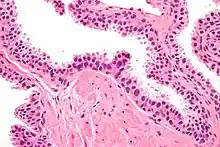

| Micrograph showing high-grade prostatic intraepithelial neoplasia. H&E stain. | |

Histology

HGPIN typically has one of four different histologic patterns:[2]

- tufted (fascicular patterning)

- micropapillary,

- cribriform and,

- flat.

Its cytologic features are that of prostatic adenocarcinoma:

- presence of nucleoli,

- increased nuclear-to-cytoplasmic ratio and,

- increased nuclear size.

Microscopically, PIN is a collection of irregular, atypical epithelial cells. The architecture of the glands and ducts remains normal. The epithelial cells proliferate and crowding results in a pseudo-multilayer appearance. They remain fully contained within a prostate acinus (the berry-shaped termination of a gland, where the secretion is produced) or duct. The latter can be demonstrated with special staining techniques (immunohistochemistry for cytokeratins) to identify the basal cells forming the supporting layer of the acinus. In prostate cancer, the abnormal cells spread beyond the boundaries of the acinus and form clusters without basal cells. In HGPIN, the basal cell layer is disrupted but present. PIN is primarily found in the peripheral zone of the prostate (75-80%), rarely in the transition zone (10-15%) and very rarely in the central zone (5%), a distribution that parallels the zonal distribution for prostate carcinoma.[7]

Several architectural variants of PIN have been described, and many cases have multiple patterns. The main ones are tufting, micropapillary, cribriform, and flat. Although these different appearances may cause confusion with other conditions, they have not been found to be of clinical importance. Rarer types are signet-ring-cell, small-cell-neuroendocrine, mucinous, foamy, inverted, and with squamous differentiation.[3]